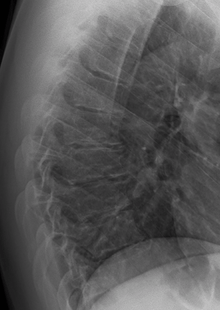

| A 20-year-old male with Scheuermann's disease, showing various measurement of kyphotic/lordotic degrees and their supplementary angles. Notice the signature 'wedging' shape of the four vertebrae in the lower thoracic area. The other vertebral bodies are otherwise normal. The measured kyphosis for this patient is ~70°. | |

Scheuermann's disease is a self-limiting skeletal disorder of childhood. Scheuermann's disease describes a condition where the vertebrae grow unevenly with respect to the sagittal plane; that is, the posterior angle is often greater than the anterior. This uneven growth results in the signature "wedging" shape of the vertebrae, causing kyphosis. It is named after Holger Werfel Scheuermann.[1][2][3]